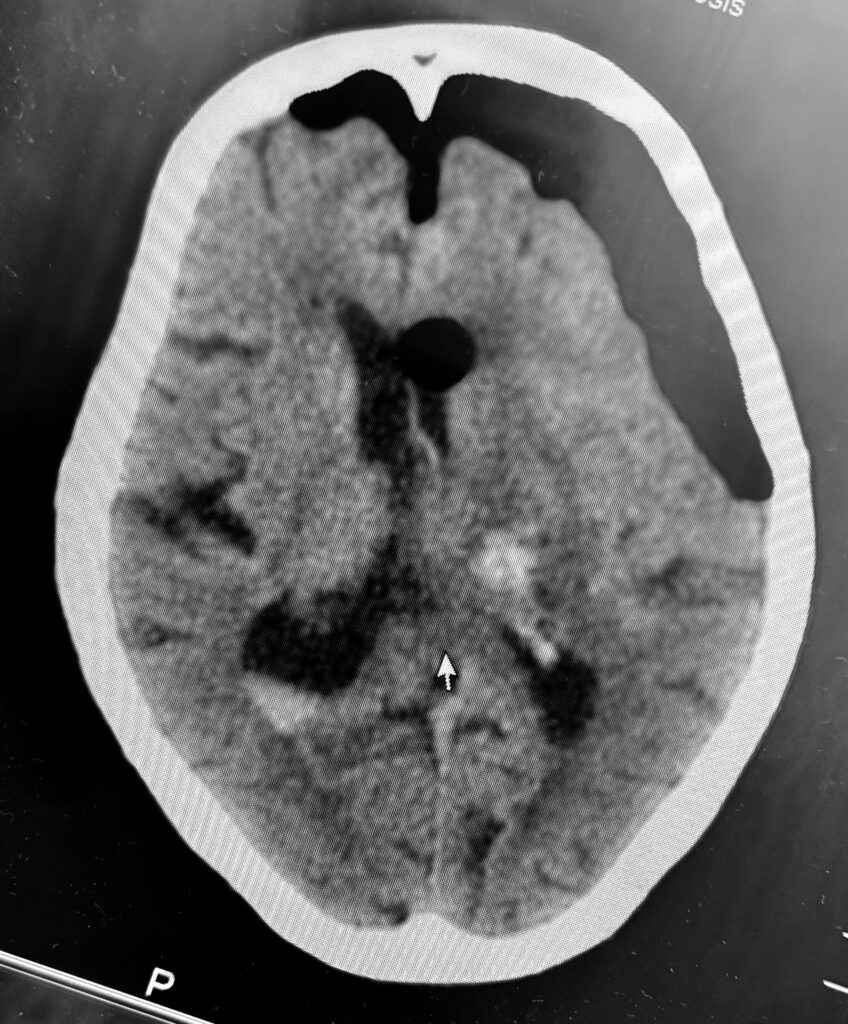

視床出血、脳室穿破の症例で、患者さんはご高齢なので内視鏡で低侵襲に血腫除去したいという要望でした。ご要望にお応えし、局所麻酔で3センチ切開し、1センチの穴を開けて血腫除去してきました。無事に血腫は取れたので今頃はリハビリテーションに励んでいることでしょう。

私は上記の写真のように個別にアプローチを決定し、透明シースを挿入し、内視鏡下に血腫除去する方法で良好な結果を得ています。ただし、エビデンスとなるとある程度の症例数を複数施設でまとめて、評価ポイントも決めて、別の治療方法との差を出して決まるので難しいです。